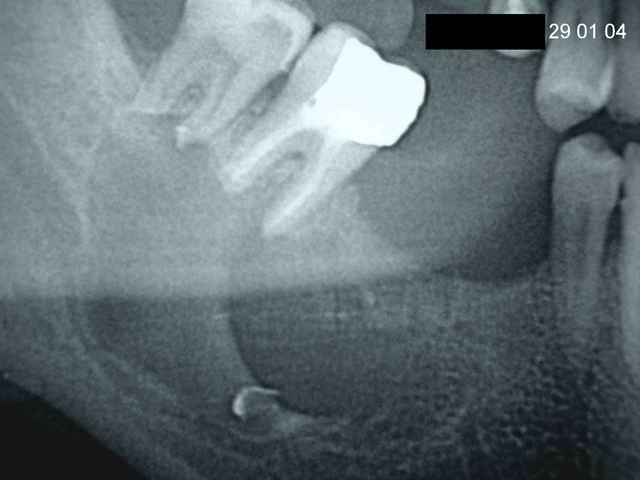

Patient vu en 2004, 50 ans, tabagique,sous curatelle, très simplet.

Ni lui, ni sa curatrice n'ont donné suite malgré mes nombreux coups de téléphone et mes mises en garde concernant les images lacunaires à la mandibule. A l'époque, j'avais trouvé une pathologie semblable dans mes bouquins de radio (même terrain déficient, même image) mais j'avoue ne pas me souvenir du nom :.<